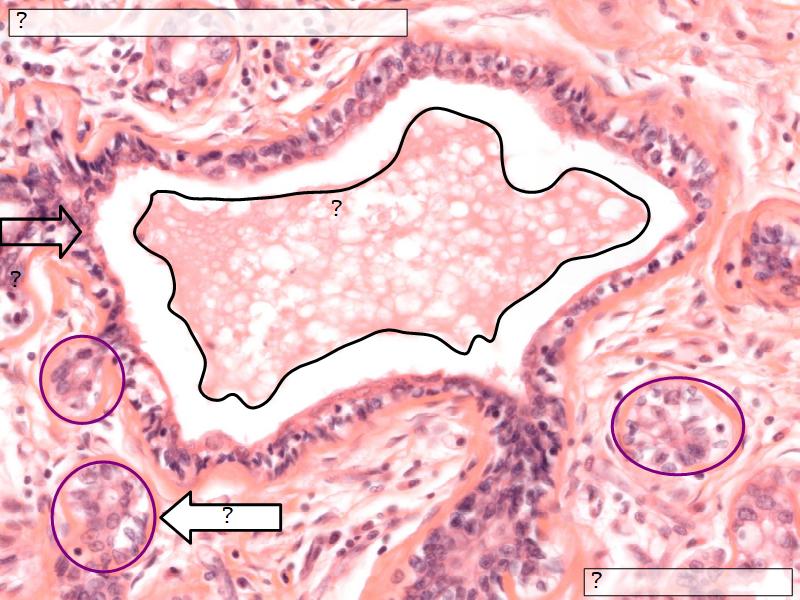

Structures

- Lactiferous sinuses

- Stratified squamous near opening on skin

- Stratified cuboidal other parts

- Lactiferous ducts

- Stratified cuboidal

- Myoepithelial cells

- Underlie lactiferous ducts in most areas

- Basal lamina

- Separate epithelial components from stroma

Active gland

- Much larger than resting phase

- Terminal ducts proliferate to form alveoli

- Alveoli

- Surrounded by incomplete myoepithelial cells